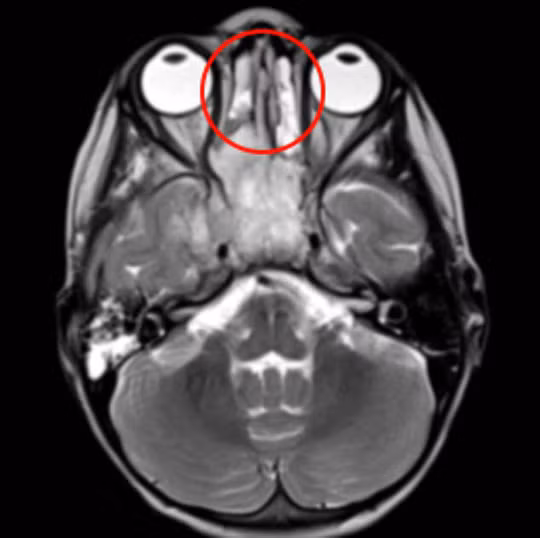

| Khối u (khoanh tròn đỏ) được thể hiện trong phim MRI - ảnh do bệnh viện cung cấp |

Cuối cùng, bé được đưa đến Bệnh viện Frimley Park để chụp MRI. Các bác sĩ đã phát hiện một khối u lớn trong khoang mũi. Bé bị chẩn đoán mắc bệnh ung thư khoang mũi hiếm gặp. Căn bệnh tấn công xương và một phần mô bên trong khoang mũi, thậm chí đã lan một ít đến vùng xương sọ, cơ hàm và cả một số tế bào não bộ.